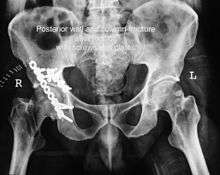

Posterior wall fracture

This is the most common variety of fracture

Cause: Occurs due to dash board injury. When a person travelling in a vehicle involved in head-on collision, the force applied over the flexed knee travels along the femur bone to the head of femur breaking the posterior wall of the acetabulum. The head of the femur is dislocated outside the joint.

Associated injury: The broken bone pieces or the dislocated head of the femur may injure the important Sciatic nerve causing paralysis of the foot; this may or may not recover depending on the extent of injury to the nerve.

The posterior wall fragment may be one large piece, or multiple pieces, and may be associated with impaction of the bone

How to diagnose: Best seen in obturator oblique view

CT scan helps in identifying impaction of bone pieces and if there are pieces in the joint

MRI may be done to identify the extent of injury to the sciatic nerve

Treatment: if the femur head is dislocated, it should be reduced as soon as possible, to prevent damage to its blood supply. This is preferably done under anaesthesia, following which, leg is kept pulled by applying traction to prevent joint from dislocating.

The final management depends on the size of the fragment(s), stability and congruence of the joint.

In some cases traction for six to eight weeks may be the only treatment required

If the fragments do not fall into place, or if there are bone pieces in the joint, or if the joint is unstable, surgical fixation using screw(s) and plate(s) is performed

Post-surgery treatment: depending on the stability achieved, the person may be allowed standing and walking with help of support for about six to eight weeks.

Full function may return in about three months.

Complications: Sciatic nerve injury and stoppage of blood supply to femoral head at the time of accident or during surgery may occur. Deep vein thrombosis and pulmonary embolism are other complications that may occur in any type of injury to the acetabulum.